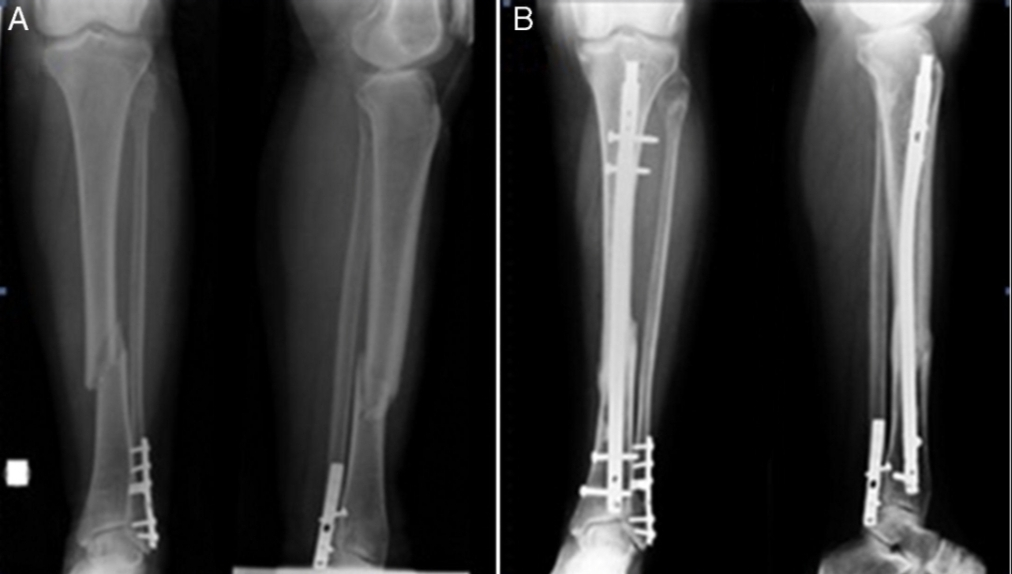

En una muestra conmovedora de solidaridad, la comunidad se unió para ayudar a financiar la operación de un hombre, quien sufrió una fractura de tibia y peroné luego de caerse de una escalera. Tras el accidente, su esposa organizó rifas y sorteos para recaudar fondos con el objetivo de cubrir los costos médicos.

Después de un arduo esfuerzo por parte de la comunidad, finalmente se logró reunir el dinero necesario para la cirugía. El hombre ya recibió las dos prótesis y actualmente se encuentra en proceso de recuperación. Sin embargo, aún queda por cubrir gastos de medicación, incluyendo antibióticos y calmantes, así también como futuros controles médicos en La Rioja, por esta razón llevarán a cabo un sorteo con 24 premios el próximo 21 de septiembre en una emisora local. Los boletos para participar están disponibles a un costo de 500 pesos cada uno.